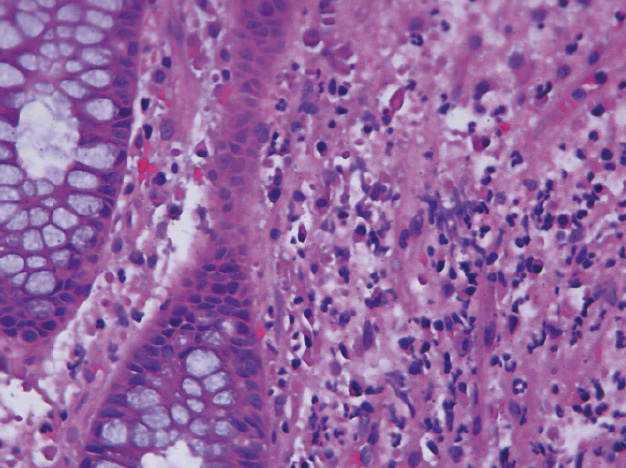

Морфологическое исследование слизистой оболочки толстой кишки проведено у 47 пациентов. Гистологическая картина отличалась значительным разнообразием. Морфологические изменения в виде умеренной или плотной лимфоплазмоцитарной инфильтрации и отек собственной пластинки слизистой оболочки выявлены у 29 (67,7%) пациентов, при этом эндоскопическая картина у них варьировала от минимальных изменений слизистой оболочки до множественных эрозий (рис. 8, 9). Специфических морфологических признаков псевдомембранозного колита, таких как вулканоподобное изменение, выявлено не было. Поверхностные эрозии и единичные криптиты отмечены у 8 (17%) пациентов. У 2 (4,3%) больных в собственной пластинке была очень плотная лимфоидная инфильтрация с примесью нейтрофильных лейкоцитов, эозинофилов с крипт-абсцессами, разнокалиберными измененными криптами, что характерно для язвенного колита. Против ожидания, тромбы в мелких венулах и артериолах обнаружены только в 2 (4,3%) случаях на фоне умеренной лимфоидной инфильтрации. Интересно, что тромбоз мелких сосудов выявлен у больных с диареей без признаков системного воспаления, с незначительными эндоскопическими изменениями в виде эрозий (рис. 10А, Б). У 5 (10,6%) пациентов значимые морфологические изменения отсутствовали. В целом следует отметить, что никакой корреляции между клинической, эндоскопической и морфологической картиной не было, кроме случаев псевдомембранозного и язвенного колита.

Рис. 8. Умеренная лимфоплазмоцитарная инфильтрация собственной пластинки слизистой оболочки толстой кишки с немногочисленными эозинофилами, умеренно выраженной регенераторной гиперплазией. Структура крипт сохранена, незначительно уменьшено количество бокаловидных клеток. Окраска гематоксилином и эозином; × 200

Рис. 9. Умеренная лимфоплазмоцитарная инфильтрация собственной пластинки слизистой оболочки толстой кишки, единичные нейтрофилы, структура крипт и бокаловидные клетки сохранены. Окраска гематоксилином и эозином; × 400